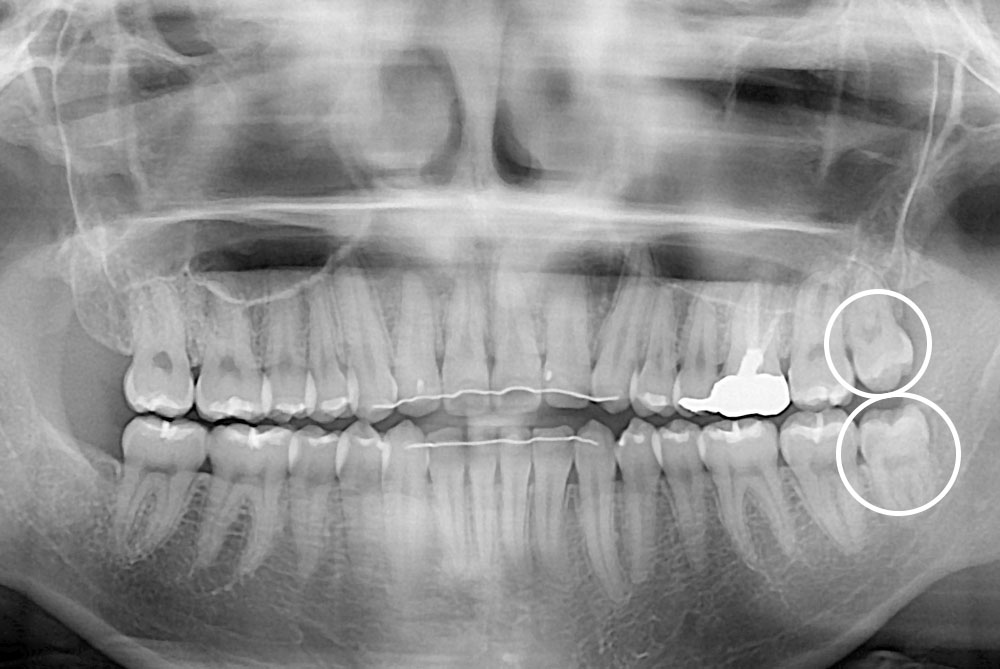

세종치과의 진심 어린 치료는 결과로 말합니다.

실제 내원하신 환자분들의 치료 전·후 사례를 확인해보세요.

모든 치료사례 전후사진은 환자분의 동의하에 촬영되었습니다.

모든사진은 동일 환자분의 전후모습을 촬영하였으며, 사진의 밝기조절 외에 임의 수정이 없음을 알려드립니다.

*수 / 시술 후 개인에 따라 결과의 차이 및 감염 등 부작용이 발생할 수 있으므로 의료진과 충분한 상담 후 결정하시길 바랍니다.